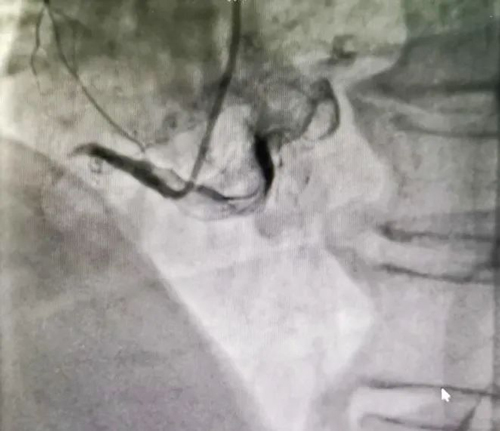

急診冠脈造影顯示RCA近段閉塞,立即送入指引導(dǎo)絲順利通過閉塞病變,恢復(fù)3級血流。

患者出現(xiàn)惡心、嘔吐

心電監(jiān)護示

室性逸搏心律

頻發(fā)室早短陣室速

血壓下降

立即加壓輸液并給予多巴胺、阿托品靜脈應(yīng)用,約10分鐘后血壓逐漸恢復(fù)正常,未再出現(xiàn)室性逸搏心律,生命體征逐漸平穩(wěn)后,于閉塞病變成功植入2枚支架,血流TIMI3級,生命體征平穩(wěn),送回病房進一步診治。